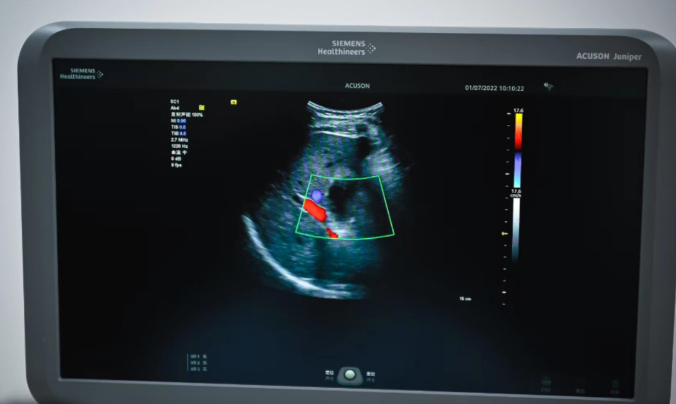

宝石花健康管理中心(洛阳)拥有通用技术宝石花医疗投资引进的联影高端多层螺旋CT、西门子高端彩超、全数字化X射线成像系统、日本高端TOPCON眼压仪、德国卡瓦口腔全景CT、德国卡瓦牙椅、六六(YZ5F)裂隙灯、超声骨密度仪、动脉硬化检测仪、ACCUNIQ人体成分分析仪等一系列先进设备。

开设有内科、外科、妇科、口腔科、眼科、耳鼻喉科、动脉硬化检测、经颅多普勒、超声科等体检诊室;并以“名医门诊”为共享平台,提供口腔、功能医学、运动康复、中医等服务及多学科会诊;拥有主检、内科学博士、医学影像学博士等高级别专家负责关键技术环节的把控。